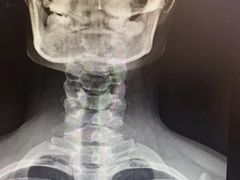

• -上海中医药大学附属曙光医院(东部)

匿名用户 | 25-01-15